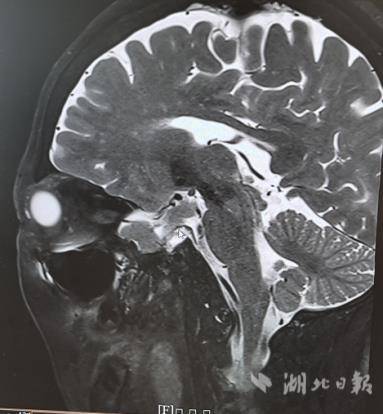

然而,影像学检查结果出乎意料。眼眶磁共振成像清晰显示,李婆婆颅内存在一巨大垂体肿物。“这个垂体瘤的占位效应,有可能是导致她甲状腺激素水平紊乱,进而引发一系列眼部症状的诱因。”杜芳解释道。